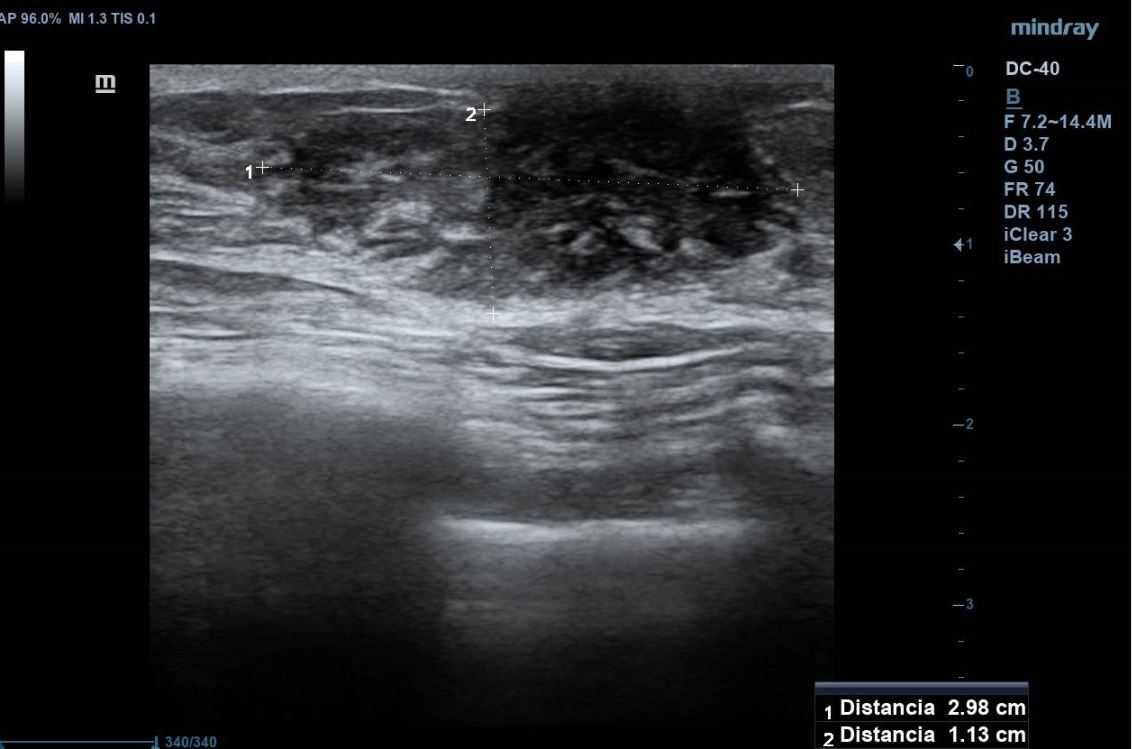

Se realiza ecografía clínica en consulta visualizando tejido de aspecto nodular de 2,98 x 1,13 cm por encima de la capa muscular, con mapa color negativo, compatible con tejido fibroglandular mamario.